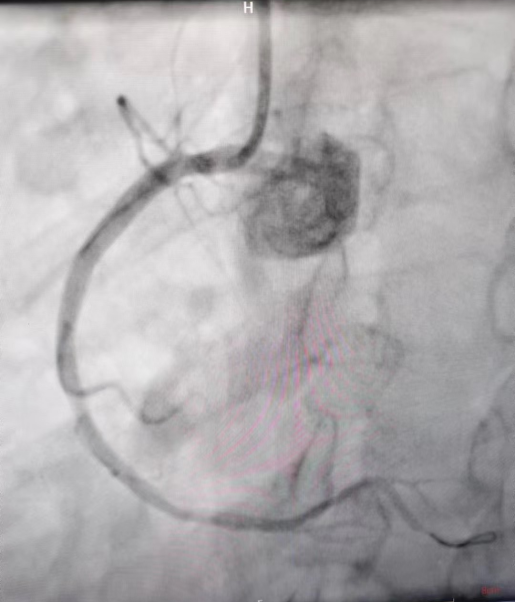

术后造影